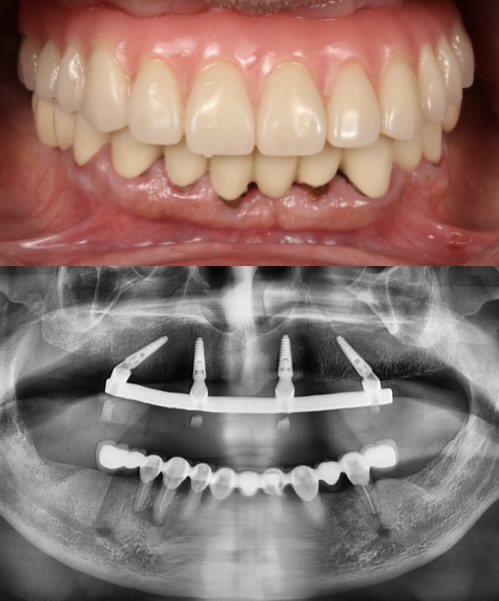

This patient transitioned from a removable denture to a fixed full-arch prosthesis using the All-on-4 technique. With strategically placed implants and immediate loading, a new confident smile was delivered within a single day. Work done by our expert team at Moral Dental Clinic

Before

After

All-on-6 in Atrophic Bone

This case involved a patient with severe periodontitis and advanced bone atrophy. Full upper arch rehabilitation was performed using the All-on-6 technique with 2 straight and 4 tilted implants to avoid the maxillary sinus. Immediate loading was done, and the final prosthesis was delivered after 6 months. Treatment successfully restored function and esthetics at Moral Dental Clinic.